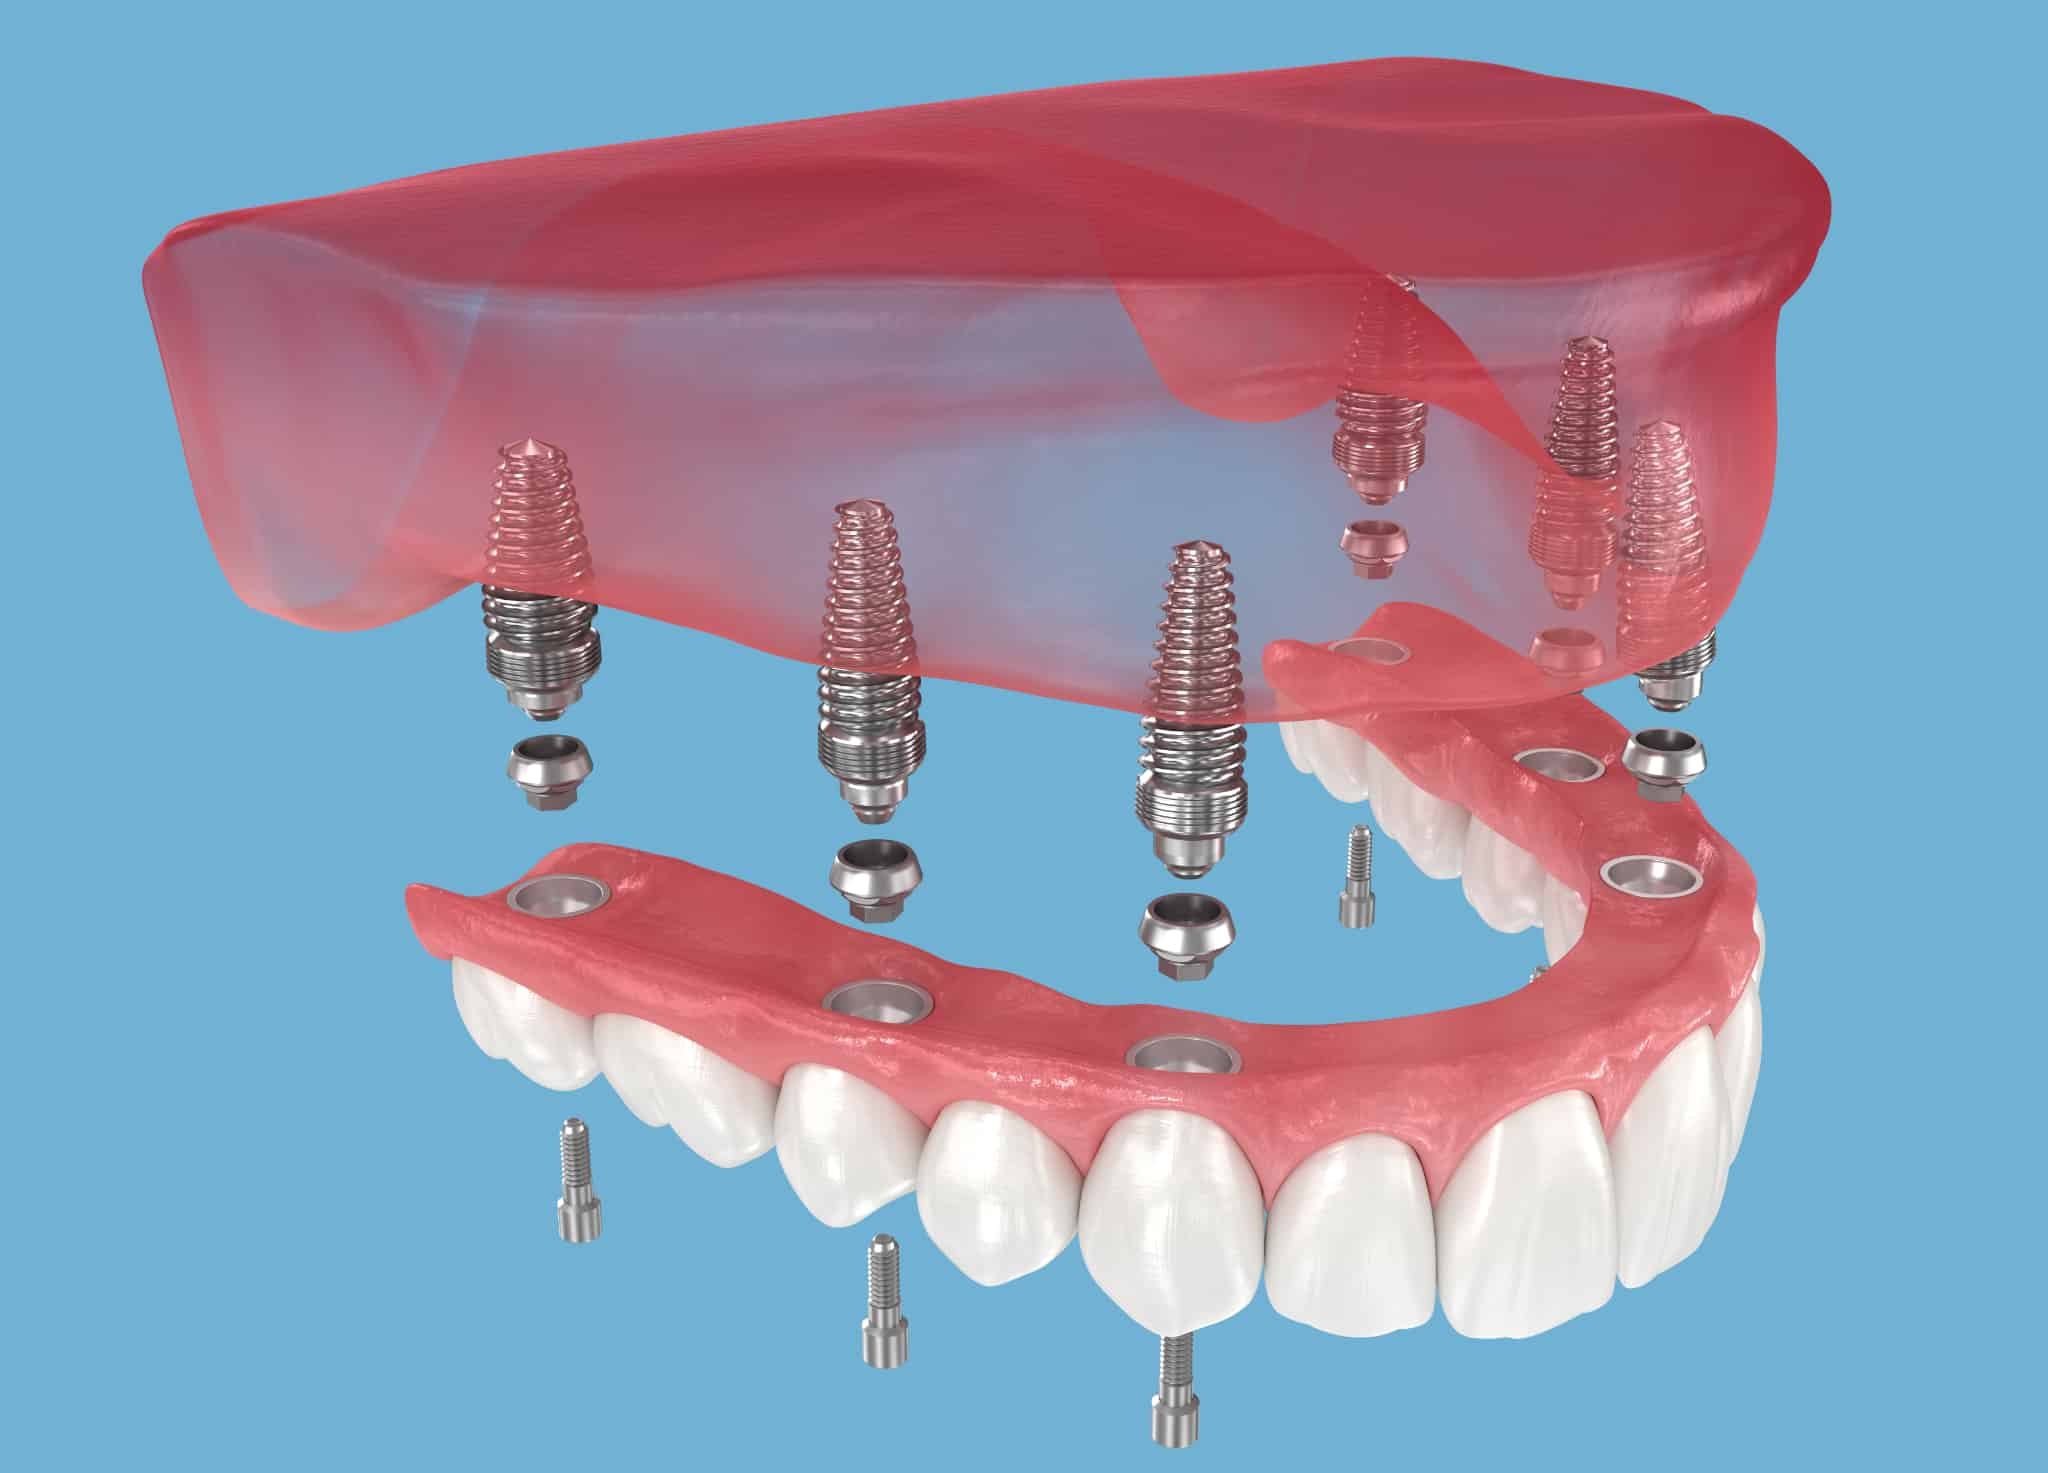

ブリッジや入れ歯との違い

・よく咬める

インプラントは治療後もこれまでと変わりなく食事を楽しむことができます。顎の骨にしっかりと固定されるため、入れ歯のように「咬みにくい」「動いて食べづらい」といった心配もありません。

・見た目が良く、違和感もない

天然歯に構造がよく似ているインプラントは、ご自分の歯と変わらないほど見た目も良好です。また装着した際の違和感もなく、食事や会話にストレスを感じることもありません。

・残っている歯を削らない

歯がない部位に直接埋め込まれるインプラントは、ブリッジのように健康な歯を削る必要がありません。他の歯に一切ダメージを与えない点が、インプラントの大きなメリットの1つです。

・他の歯に負担がかからない

ブリッジや入れ歯は、その維持力や咬む力を残っている他の歯や粘膜に依存する必要があります。しかしインプラントは硬い顎の骨に支持されるため、周囲の歯や歯ぐきに余計な負担をかけることがありません。

・外科手術が必要

インプラントの治療ではフィクスチャ—(人工歯根)を顎の骨の中に埋め込む手術が必要となります。

インプラントのメリット

◆自分の歯に近い感覚で、しっかり噛める

◆入れ歯のように外れたり、ズレたりしにくい

◆見た目が自然で、口元の印象が若々しくなる

◆あごの骨が噛む力を受けることで、骨が痩せにくくなる